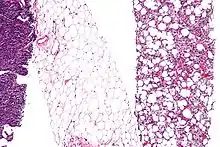

Micrograph of a liposarcoma with some dedifferentiation, that is not identifiable as a liposarcoma, (left edge of image) and a differentiated component (with lipoblasts and increased vascularity (right of image)). Fully differentiated (morphologically benign) adipose tissue (center of the image) has few blood vessels. H&E stain.